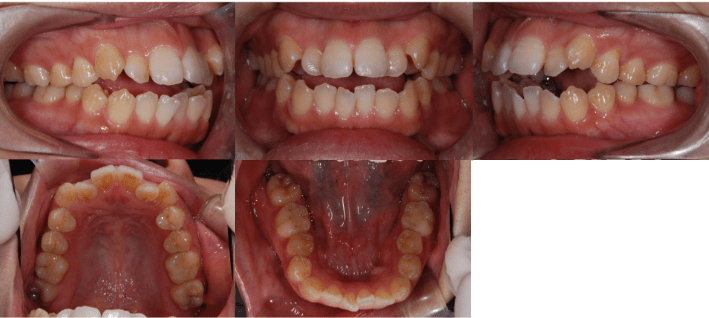

治療後

• 初診時年齢:28歳4ヶ月

• 主訴:前歯のかみ合わせ

• 診断:開咬

• 治療内容:小臼歯4本を抜歯した後に、マウスピース型カスタムメイド矯正歯科装置(製品名インビザライン 完成物薬機法対象外)を使用して主訴である開咬の改善を行いました。

• 治療期間:2年

• リスク:矯正治療による歯の移動に伴う痛み、歯根吸収、虫歯

• 費用:80万円